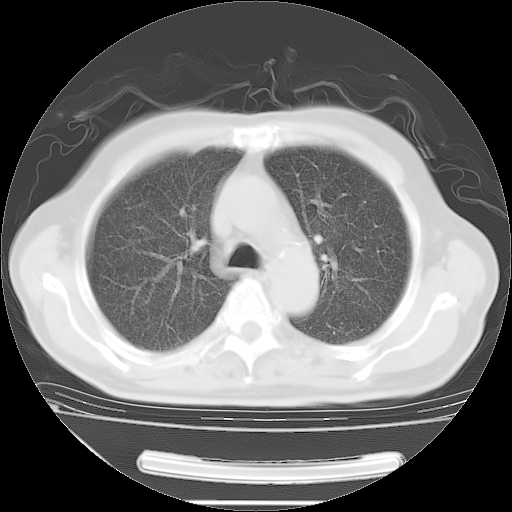

今天复查肺部CT,发现双肺广泛磨玻璃样改变。所以我把3月19日和5月9日相隔50天的肺部CT上传。请大家会诊。

5月9日肺部CT(在4月27日齐鲁医院肺部CT描述部分肺组织磨玻璃样改变,12天后肺组织广泛磨玻璃样改变)

2009年5月9日肺部CT

大致读了系列胸部CT:纵隔窗无明显异常,肺窗:从4、27至今:主要是双肺中下野外带可见毛玻璃样改变,目前处于急性肺泡炎阶段,至于原因考虑1、结替组织或胶原血管性疾病所致?2、恶性疾病如恶组在肺部所致的表现或细支气管肺泡癌?3、药物或其它原因如肺蛋白沉着症所致肺泡炎目前不太可能?总之,明天就去请我院的呼吸科、感染科、血液科和临免专家会诊哈。